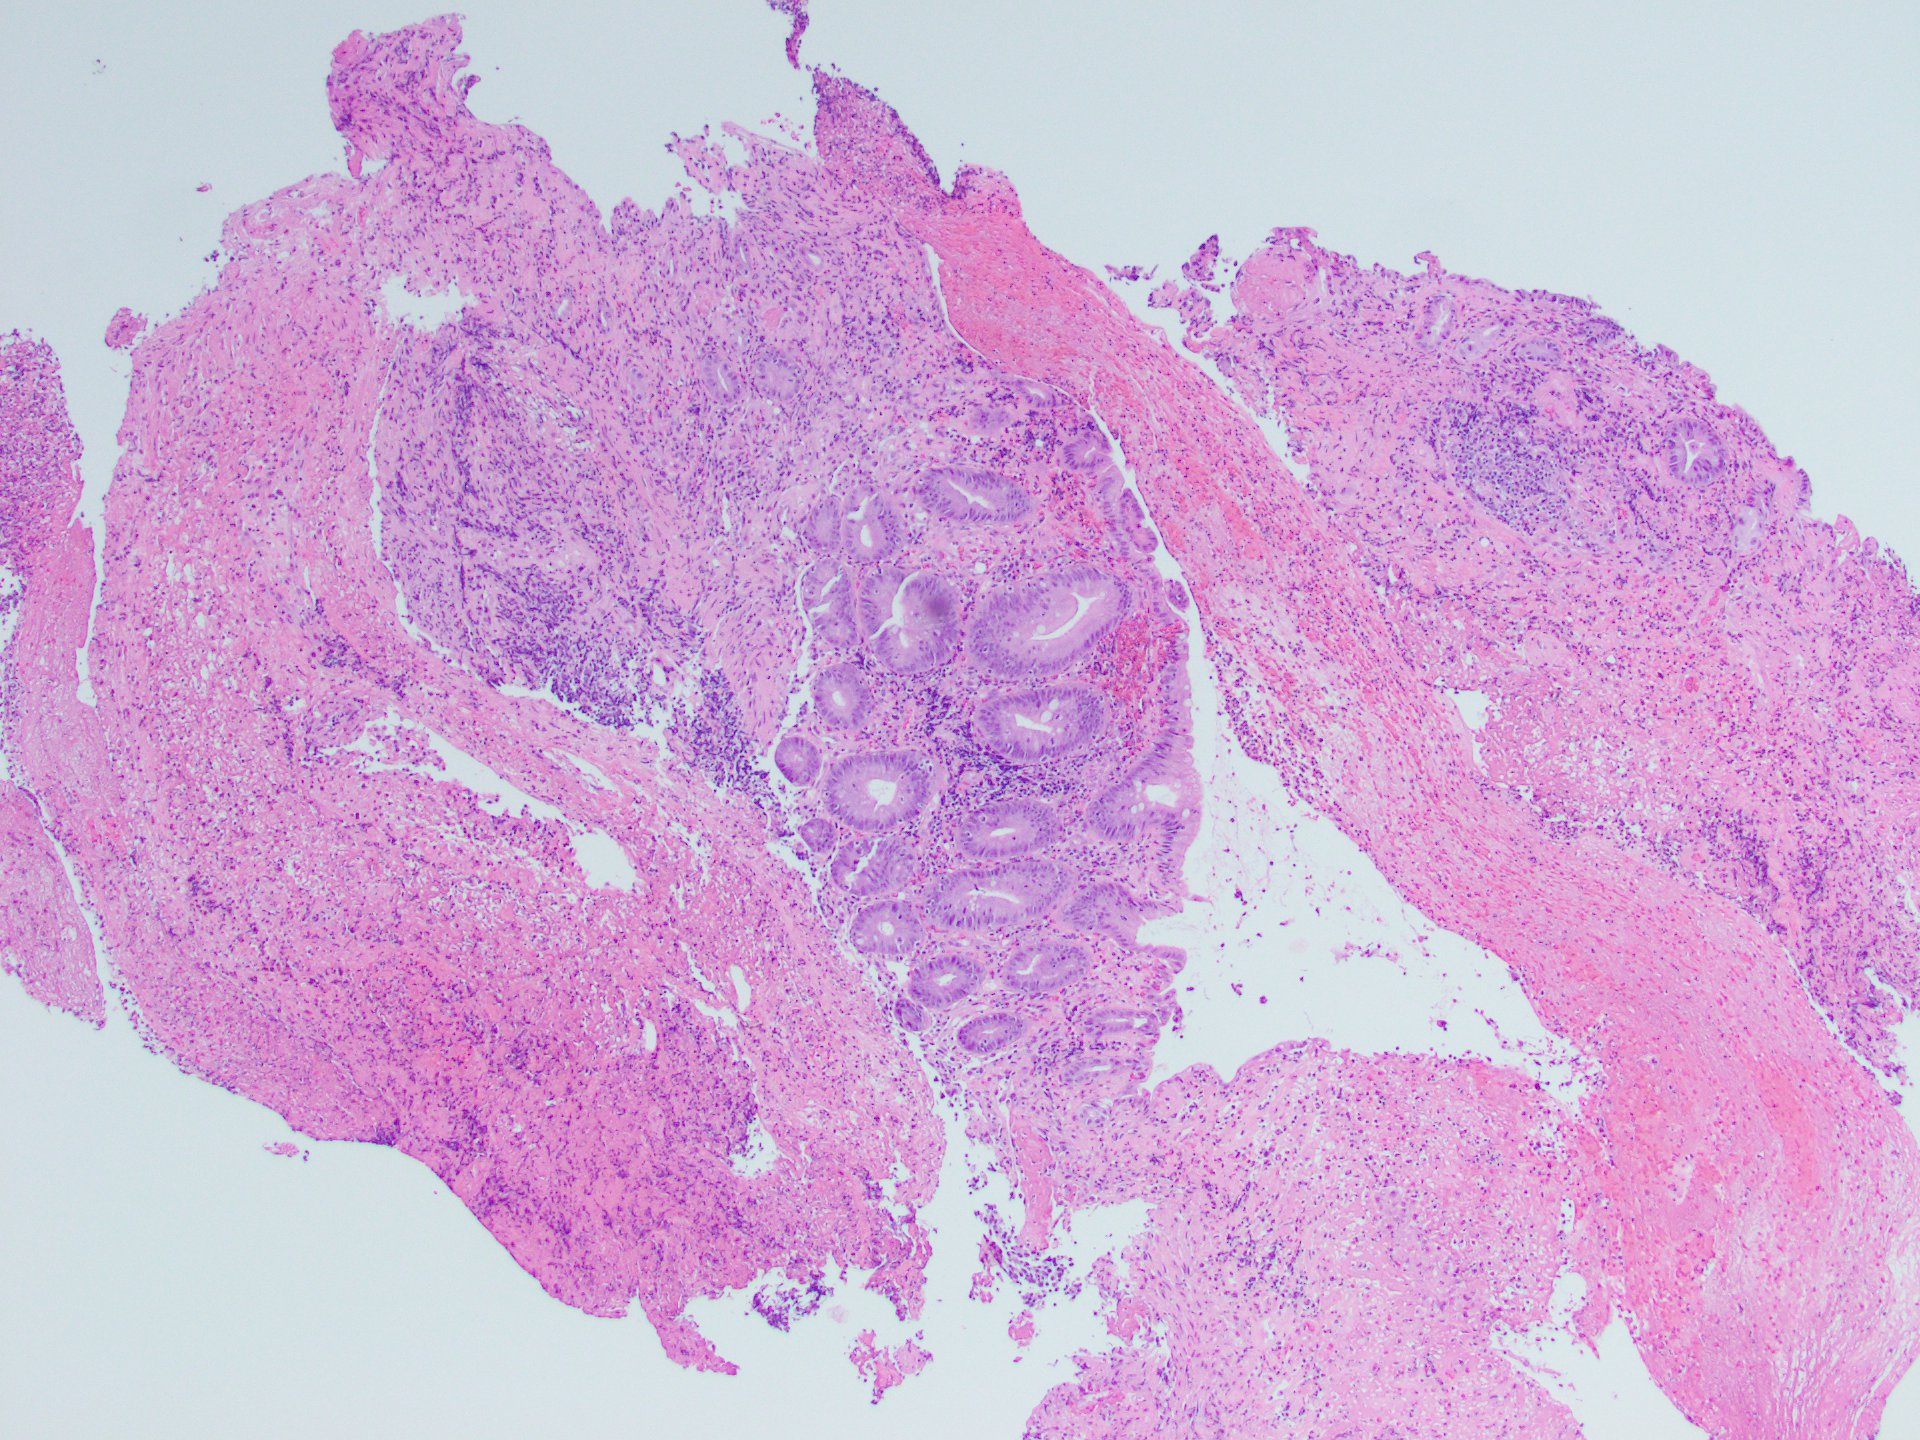

A colonoscopy was performed identifying a mass-like lesion at the ileocecal valve (Figure A). Biopsies were taken of the mass-like lesion, as well as additional samples throughout the colon. The biopsies demonstrated hyalinized lamina propria, atrophic crypts, ulceration, and active inflammation (Figures B and C). The random colon biopsies histologically demonstrated features of lymphocytic colitis (Figures D and E).